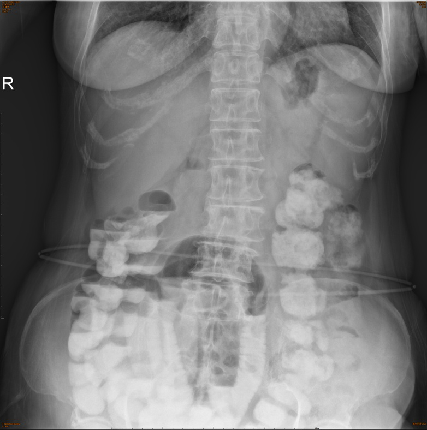

2017.9 腹痛,腹部平片提示低位小肠不全梗阻,予保守治疗

2017.12 CT: :"直肠癌根治术后",左下腹造瘘后,前下腹壁疝,小肠系膜渗出改变,不全小肠梗阻可能,腹盆腔少量积液;子宫多发肌瘤考虑;回盲部、腹膜后、胃小弯侧及肠系膜多发小及稍大淋巴结;肝脏囊性灶;脾大,副脾;附见右侧胸腔积液部分包裹。

2017.12.16因“肠梗阻”于公立医院普外科行“剖腹探查+肠粘连松解+回盲部切除术”.